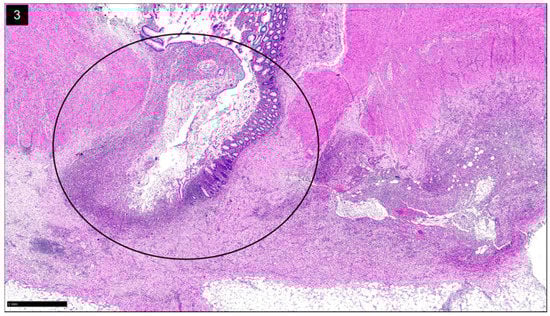

SCAD is characterized by nonspecific segmental inflammation in the sigmoid colon surrounded by multiple diverticula [4,11,12,25]. The initial presentation is often rectal bleeding and in some, diarrhea or abdominal pain [12]. SCAD is typically benign and self-limited [4]. SCAD differs from diverticulitis because the individual diverticula are not involved; histologically, this shows inflammation within the interdiverticular mucosa rather than the diverticular orifices [4,12]. Additionally, a chronic active colitis pattern of injury with crypt distortion and cryptitis is seen on histology (Figure 2). Its prevalence varies between 1.15% and 11.4% among those diagnosed with diverticular disease [11].

Figure 2.

Diverticular Disease Associated Colitis, a.k.a. Segmental Colitis Associated with Diverticulosis (SCAD): H&E stain shows chronic active colitis (inset) in a segment of sigmoid colon with diverticular disease (Circle) (H&E, ×15).